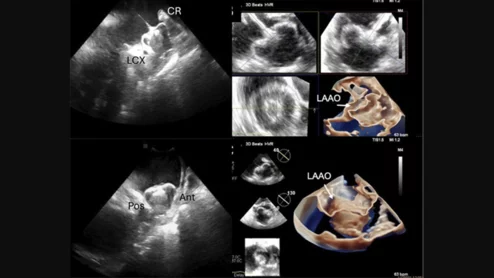

SCAI ICE position statement

ICE is gaining momentum as a helpful imaging option during structural heart interventions, according to a new SCAI position statement. TEE and TTE remain incredibly important, but there are times when ICE can provide the guidance necessary.